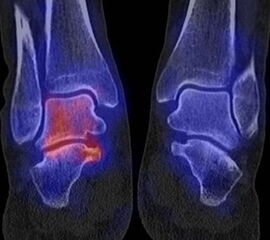

Abbildung 1.8.a und b: Akute Arthritis bei bekannter Gicht in beiden OSG: links die Früh-/Weichteilphase; rechts die Mineralisations­phase. Deutliche, entzündlich bedingte Mehranreicherungen in der Früh-/Weichteilphase. In der Mineralisation­sphase erkennt man die entzündliche Mitreaktion der subchondralen Gelenkabschnitte.

Zum Lesen der Bildbeschreibung und zur Vollansicht bitte das Bild anklicken. Bild: H. C. Rischke

Abbildung 1.8.c - e: Akute Arthritis in beiden OSG, rechts > links. Im SPECT/CT erkennt man die Mitreaktion der subchondralen Gelenkabschnitte. Die Arthritis ist so akut, dass (noch) keine ossären morphologischen Veränderungen im CT abgrenzbar sind.

Zum Lesen der Bildbeschreibung und zur Vollansicht bitte die Bilder anklicken. Bilder: H. C. Rischke